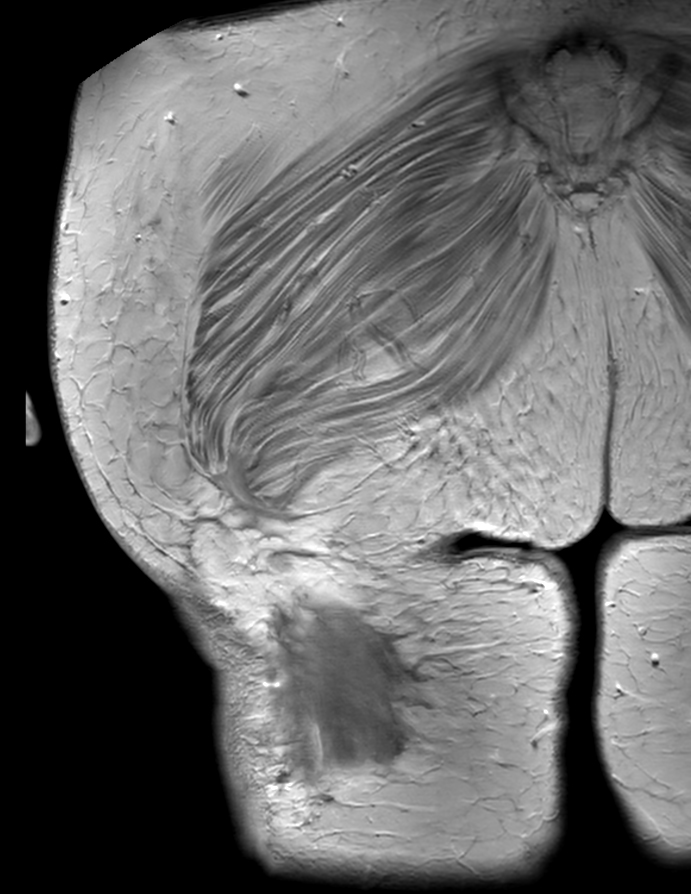

Coronal T1w TSE

Coronal T1w TSE +gado